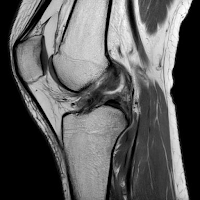

Nadat ik mezelf had verdiept in wie mij op weg zou kunnen helpen, kwam ik in het voorjaar van 2025 terecht bij Jacco Zijl van OrthoCareClinics. Vanaf het eerste moment had ik vertrouwen in zijn aanpak. Jacco was goed voorbereid, nam uitgebreid de tijd, stelde vragen, dacht mee en handelde doortastend. Hij concludeerde al snel dat het waarschijnlijk ging om een notch impingement – een te nauwe ruimte in de femorale notch die belemmerde dat de kruisband vrij kon bewegen en daarmee vastliep, met een extensiebeperking tot gevolg. “Met deze knie ga je de eindstreep niet halen”, waren zijn woorden. Een notchplastiek zou mijn probleem kunnen oplossen. Het klonk logisch en het voelde alsof we eindelijk dichterbij de oplossing kwamen. Een operatie werd gepland. Ik fleurde op en kreeg weer energie, want er was eindelijk nieuw perspectief.

| Notch impingement |